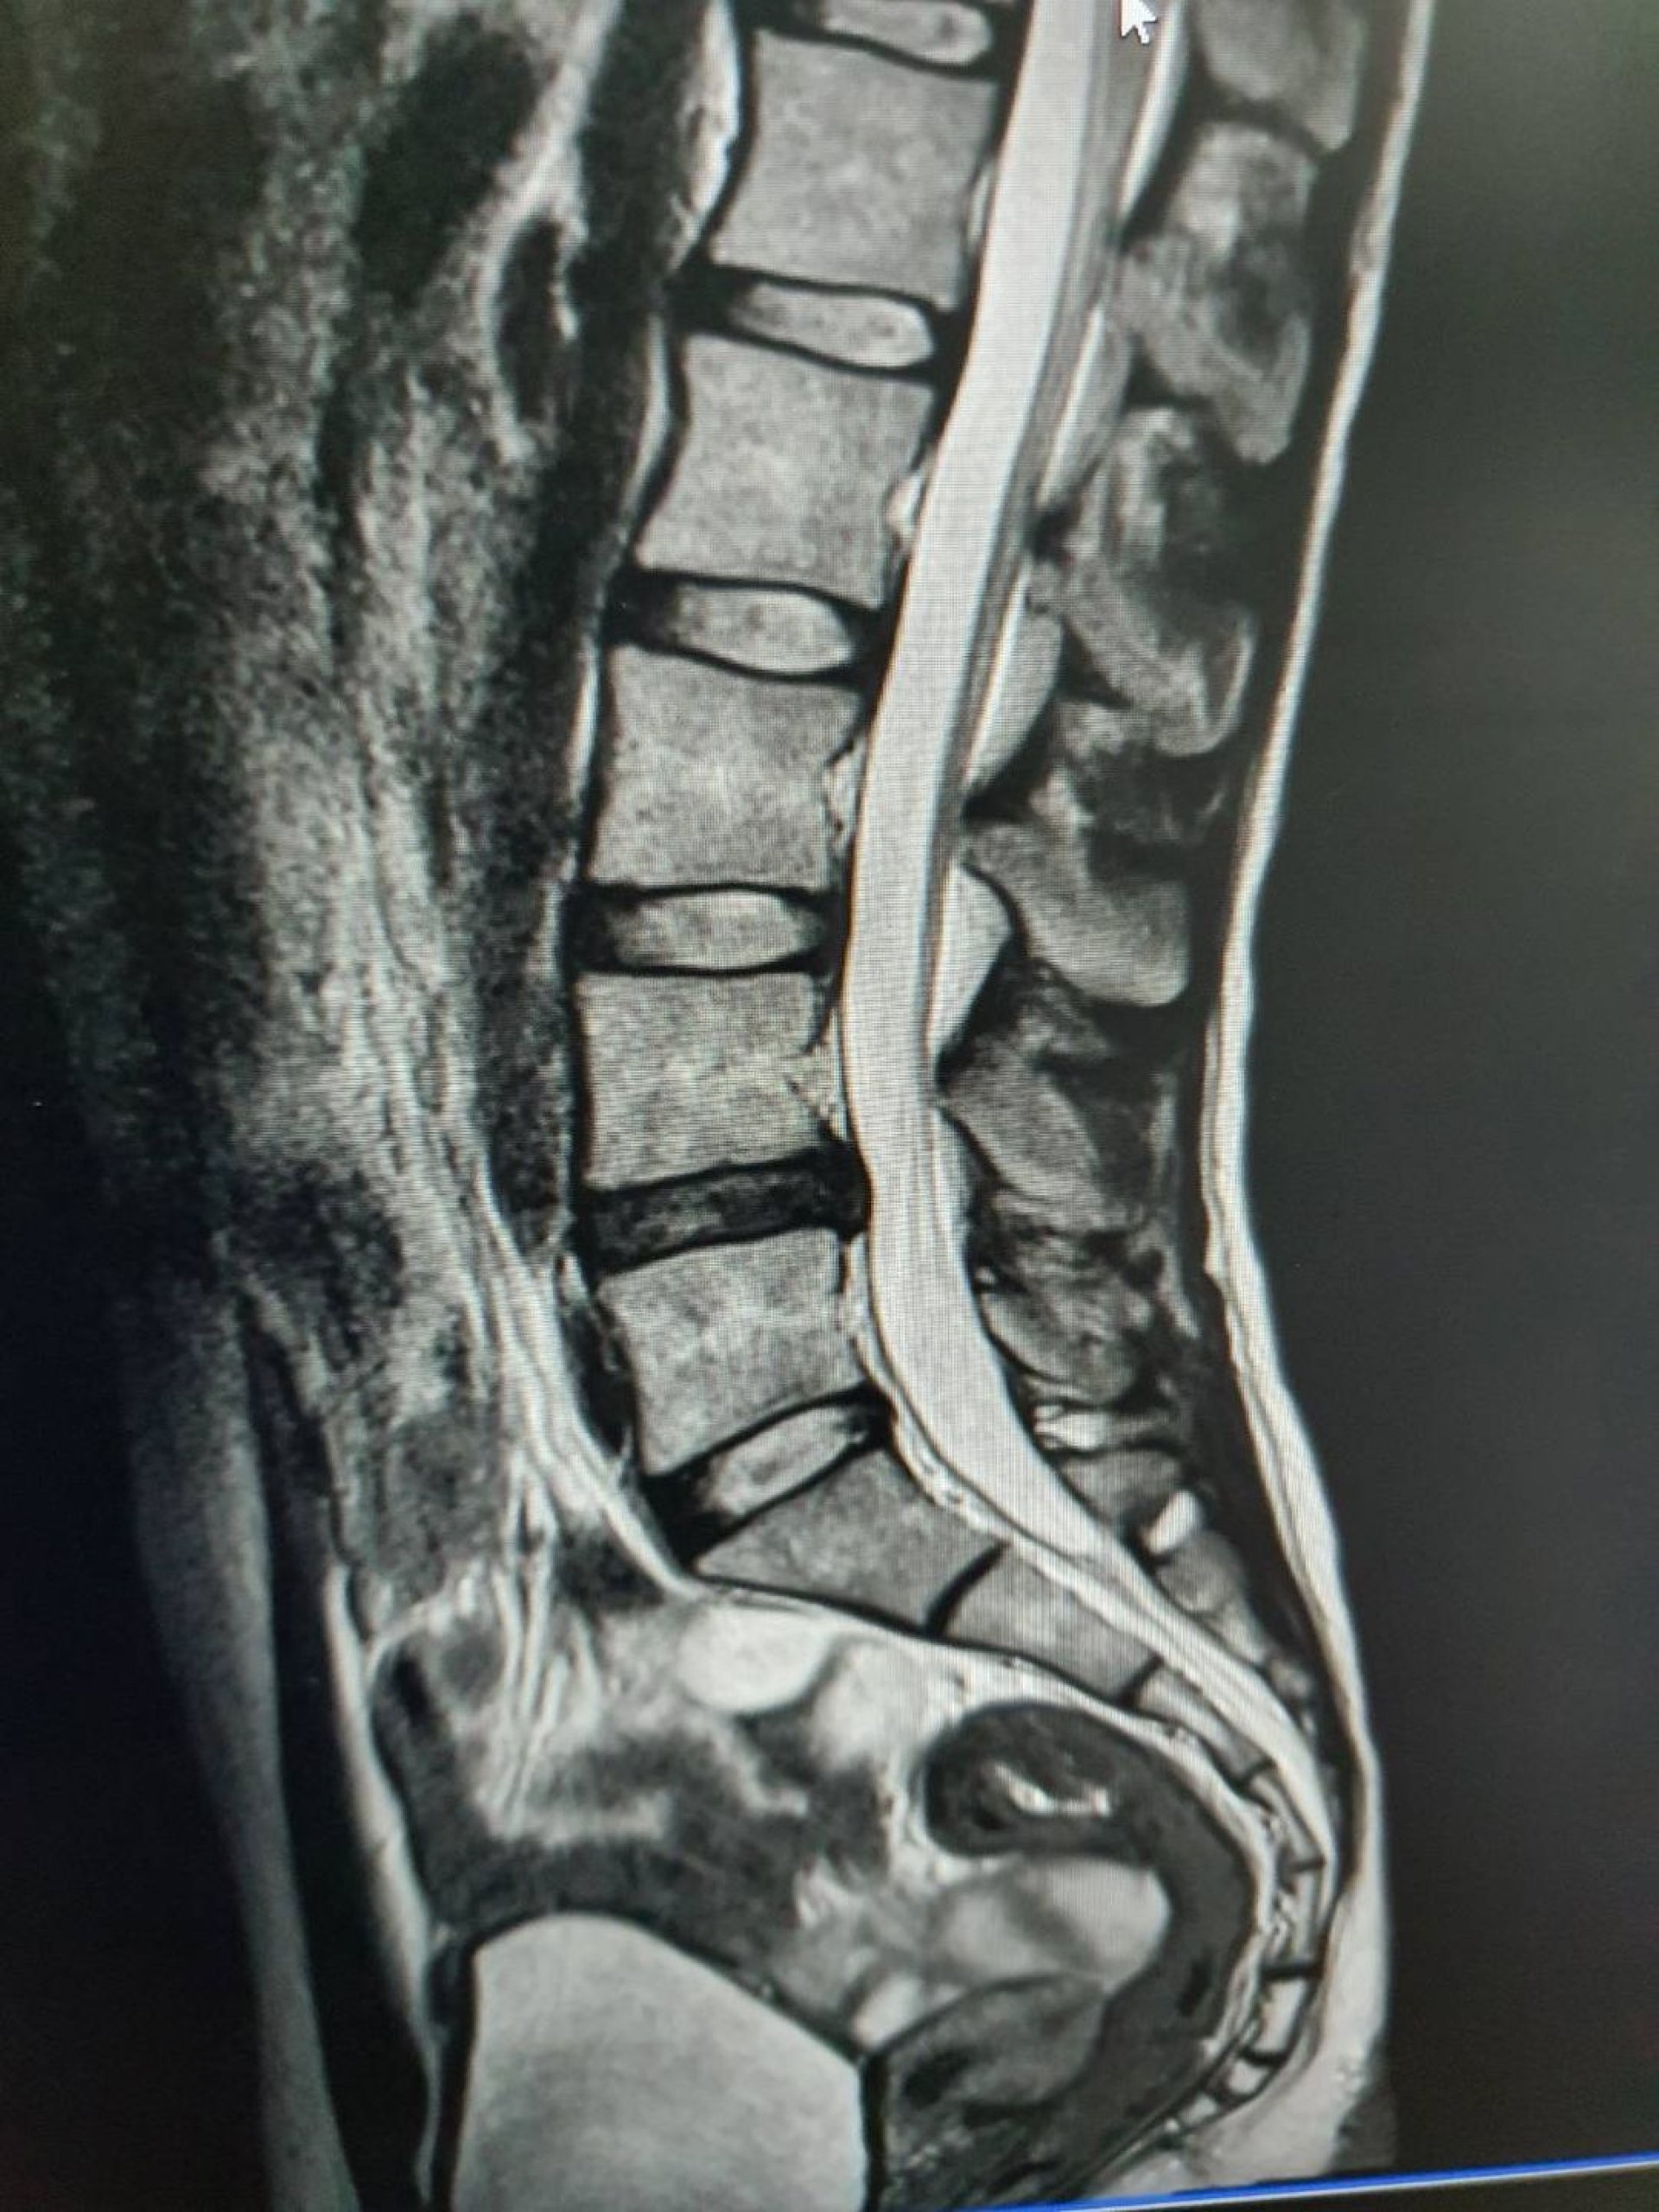

วันนี้เป็นเคสหมอนรองกระดูกปลิ้นกดทับเส้นประสาท (HNP) ซึ่งจากภาพจะเห็นว่ามีหมอนรองหนึ่งอันที่ไม่เหมือนอันอื่น นั่นคือหมอนรองกระดูกของข้อที่ 4ต่อ5 โดยคนไข้รายนี้เกิดการบาดเจ็บจากการไปออกกำลังท่า Deadlift เมื่อประมาณ 1 ปีก่อน โดยคิดว่าเป็นการเจ็บหลังธรรมดา มีไปพบคุณหมอแต่ก็ไม่ได้สงสัยอาการหมอนรองเลย คนไข้ก็ทานยาและพัก หลังจากนั้นอาการก็ดีขึ้น เลยกลับไปออกกำลังกายเหมือนเดิม แต่ตลอดช่วงที่ผ่านประมาณ 1 ปีก็เป็นๆหายๆ ออกกำลังกายได้ไม่เหมือนเดิม

จนสุดท้ายเข้ามารักษาที่คลินิก ด้วยอาการ "เจ็บตรงเชิงกรานมาก นั่งนานและเดินนานไม่ได้" หลังจากที่คลินิกรักษาไปซักพักหนึ่งอาการไม่ได้ดีขึ้นเท่าที่ควรจะเริ่มสงสัย อาการหมอนรอง จึงตกลงกับคนไข้ให้ไปทำ mri สรุปก็เป็นอาการหมอนรองกระดูกปลิ้นจริงๆ

ซึ่งความยากในการรักษานั้นคือ ณ ปัจจุบัน อาการของคนไข้ถูกกระตุ้นง่าย จากการใช้ชีวิตประจำวัน โดยการรักษาของทางคลินิกนั้นใช้เทคนิค Mckenzie เป็นหลัก เพื่อดันหมอนรองกลับเข้าไป ไม่ให้หมอนรองปลิ้นไปกดทับเส้นประสาท ซึ่งอาการคนไข้ก็ดีขึ้นตามลำดับ